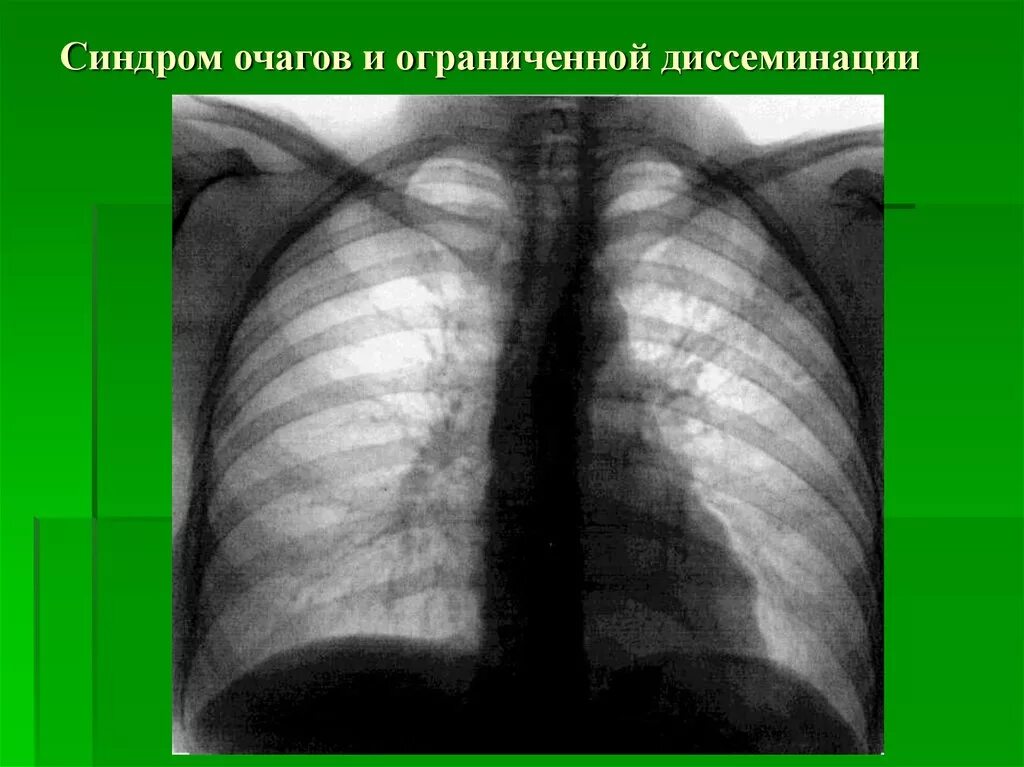

Синдром диффузной